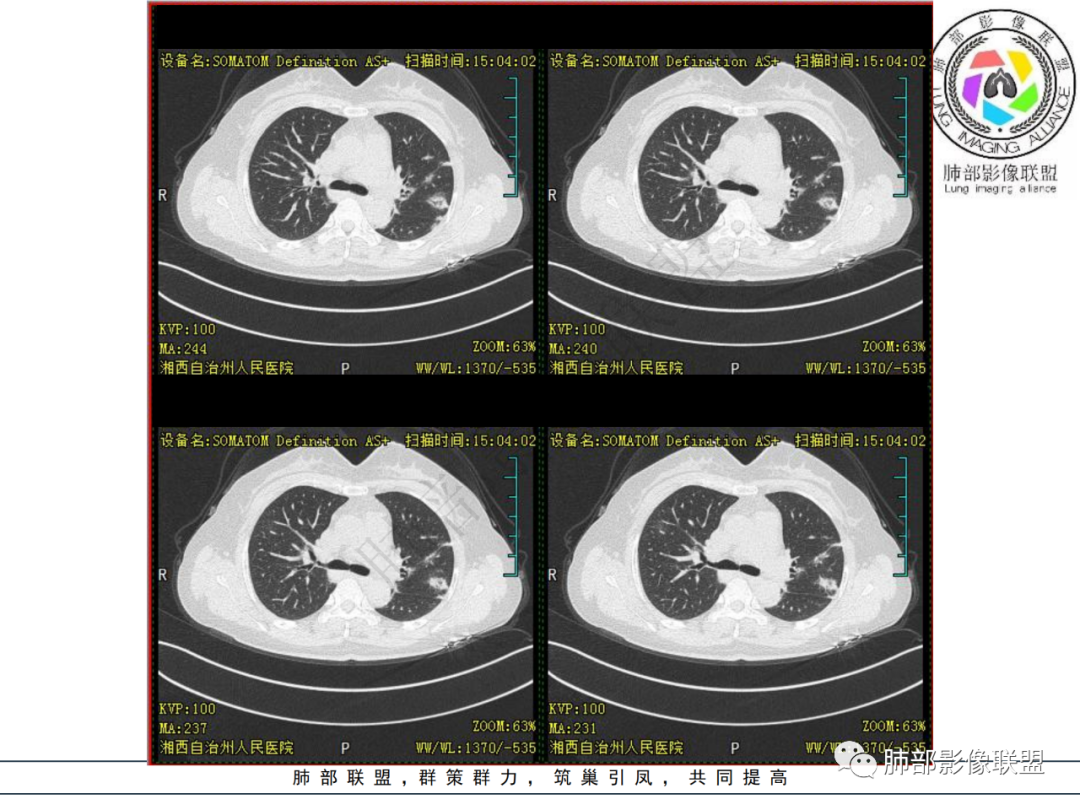

中年妇女,类风湿性关节炎病史,RF升高,感染性指标正常,双肺散在多发结节、斑片、条片灶,边缘欠清晰,大部分胸膜下分布,部分反晕,考虑RA-ⅠLD ,OP样改变

中年女性,有类风湿关节炎病史,双肺内及胸膜下见多发结节,条索状及小实变影,部分结节病灶垂直支气管血管束生长,部分结节病灶内见偏心性空洞形成,病灶收缩力弱,病灶形态多样,部分可见纤维化样改变,整体符合Op表现,结合患者病史,考虑类风湿结节,隐球菌感染不能排除。

中年女性,类风湿关节炎病史,双肺散在结节影,胸膜下分布为主,部分可见小空洞影,部分可见索条影,OP样改变,考虑类风湿结节,鉴别隐球菌

双肺散在多发结节及斑片,边缘欠清晰,胸膜下分布为主,部分内可见支气管扩张,妇女,类风湿性关节炎病史,RF升高,感染性指标正常,考虑RA-ILD,鉴别淋巴瘤。

中年女性,确诊类风关一年余,无发热及呼吸道症状,实验室检查无特殊。

双肺多发斑片影、结节影,胸膜下分布为主,部分沿支气管血管束分布,病灶大部分边缘平直。

复查CT病变进展,间隔时间不详。

总体倾向非感染非肿瘤性病变。

考虑:CTD-ILD(OP型)可能

鉴别:类风湿结节,一般与皮下结节同步出现。

女性,49岁,多关节肿痛一年余,类风湿因子升高。CT示双肺多发斑片影结节影,胸膜下为主,部分内部可见支气管扩张,部分内部似见小空洞影,复查CT进展,首先考虑为RA—ILD,鉴别CTD—ILD

双肺多发结节状及斑片状不均质磨玻璃病灶,胸膜下分布为主,边缘有收缩、凹陷,部分反晕,病灶内可见支气管扩张。中年女性,类风湿关节炎,感染指标正常。类风湿结节?隐球菌?

女,49岁,类风湿因子升高,影像双肺斑片及小结节影,胸膜下分布为主,部分病灶内支气管扩张,双侧胸膜增厚,复查病灶增多增大,考虑RA_ILD。

女性,49岁,多关节肿痛1年余。RF升高。胸部CT:双肺多发斑片影、结节影,胸膜下为主,部分沿支气管血管束分布,大小不等,部分病灶内支气管扩张,部分呈反晕,部分呈楔形宽基底贴附胸膜,复查CT进展,考虑:CTD—ILD?OP?鉴别血管炎、HP、肺梗、曲霉等。

中年女性,多关节肿痛一年,类风湿因子增高,双肺及胸膜下可见多发大小不一结节,部分呈楔形,以胸膜下分布为主,边缘平直,部分病灶分布于支气管血管束,部分可见空气支气管征、反晕征,复查病灶进展,类风湿结节?OP?

1.中年女性,发现双肺多发病变,且增多增大。

缺乏呼吸道症状及中毒症状,实验室炎性指标不高

既往多关节肿痛一年余,被诊断“类风湿”。此次就医无关节肿痛。

2.双肺多发片状影,胸膜下分布为主,部分沿支气管血管束分布,边界不清,实性及磨玻璃密度,趋于柔和,可见支气管进入或穿行,未见空洞、钙化及树芽等。部分病灶显示反晕。

3.未见腔积液。

4.双肺门及纵隔未见增大淋巴结。